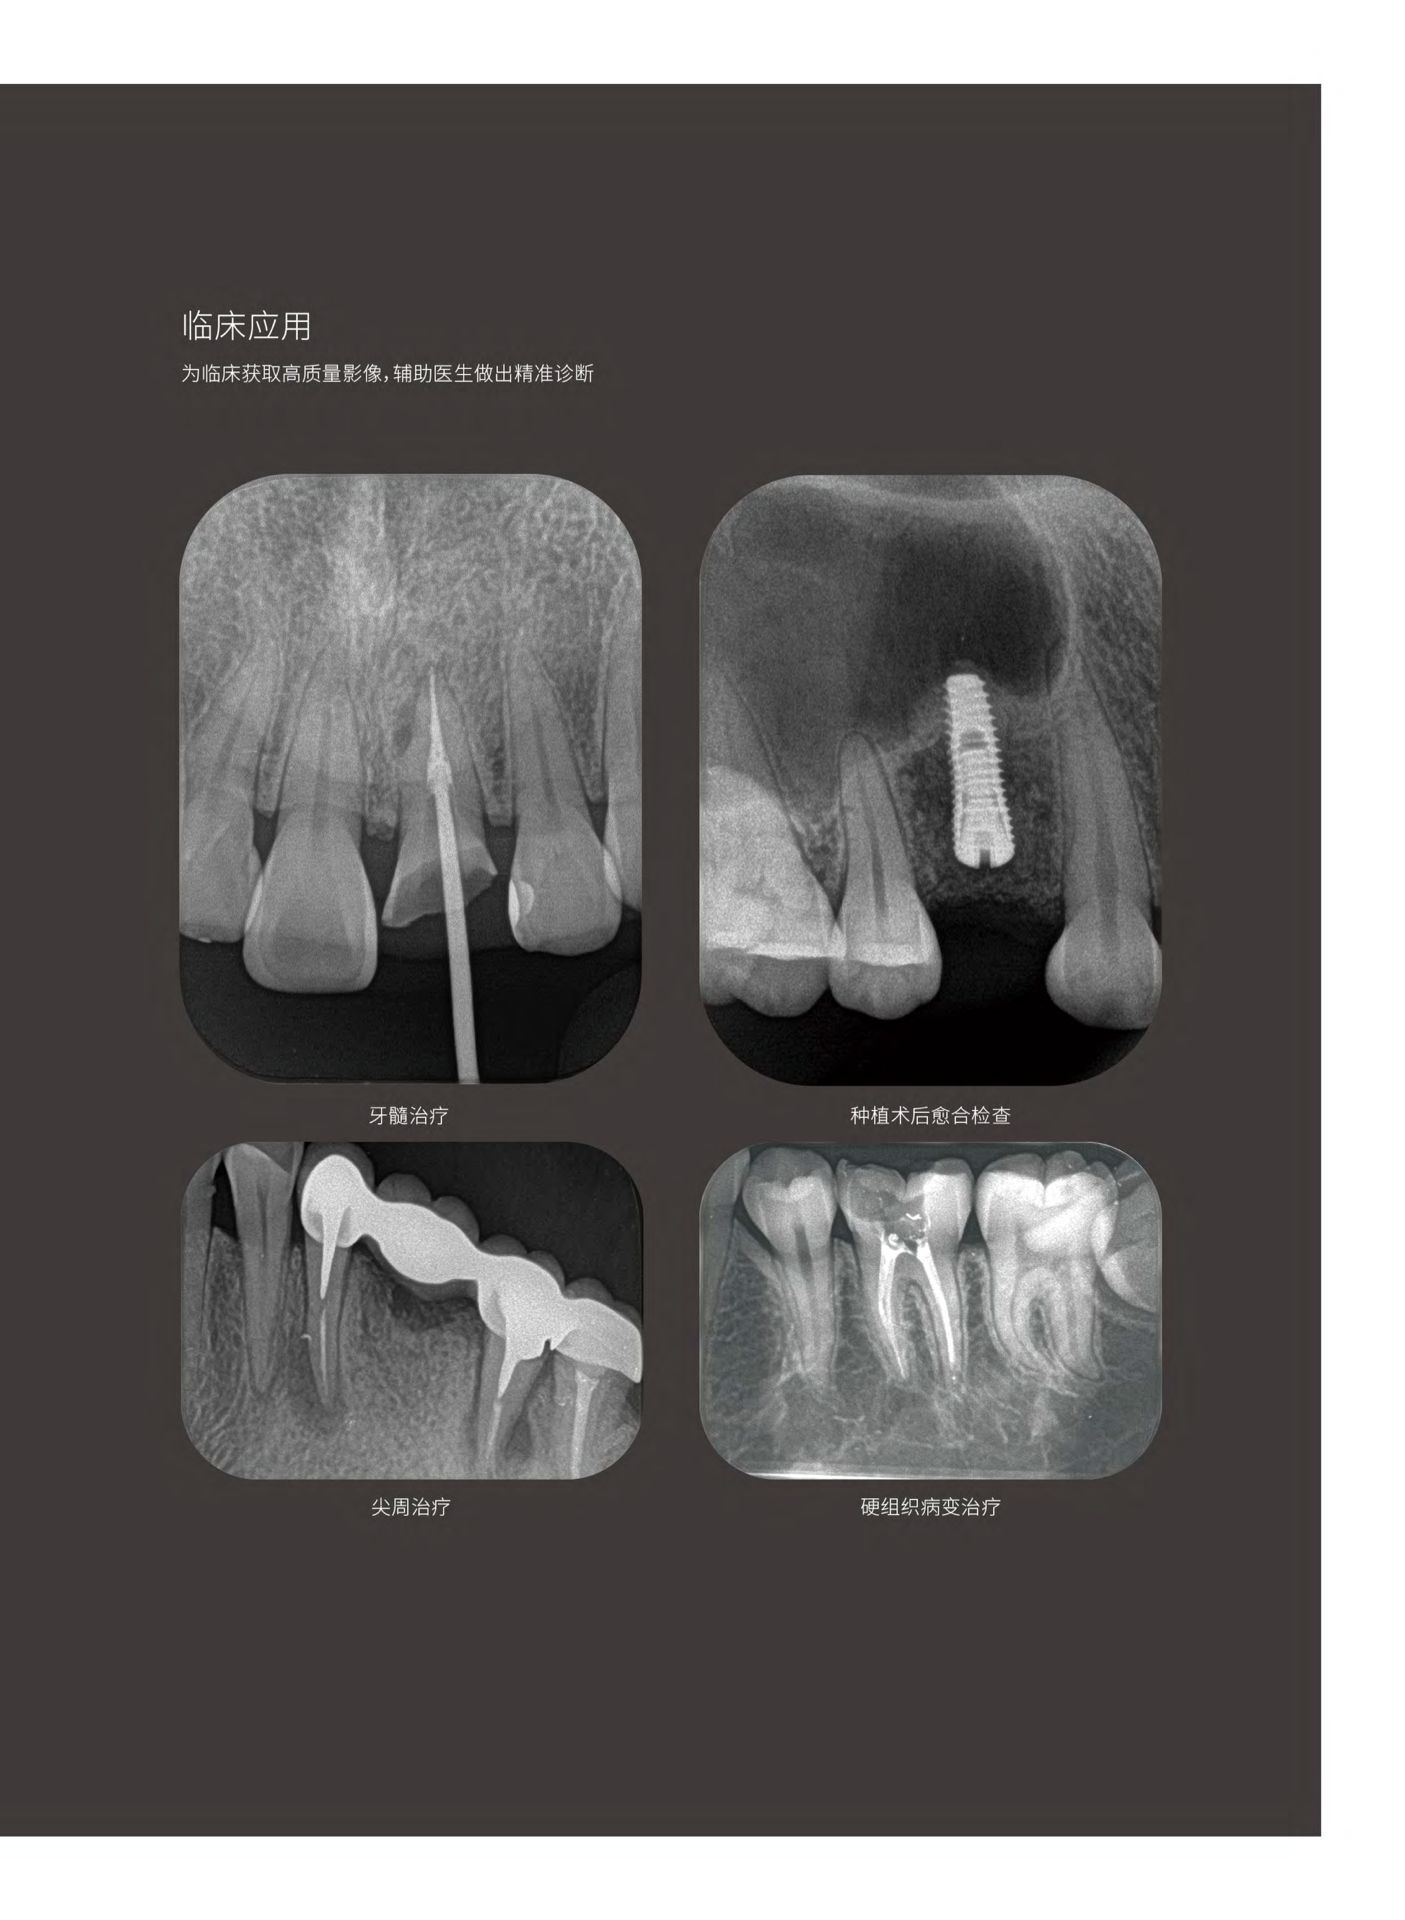

牙片宝牙智宝拍片机牙片宝磷光片无线数字口内影像板扫描处理系统